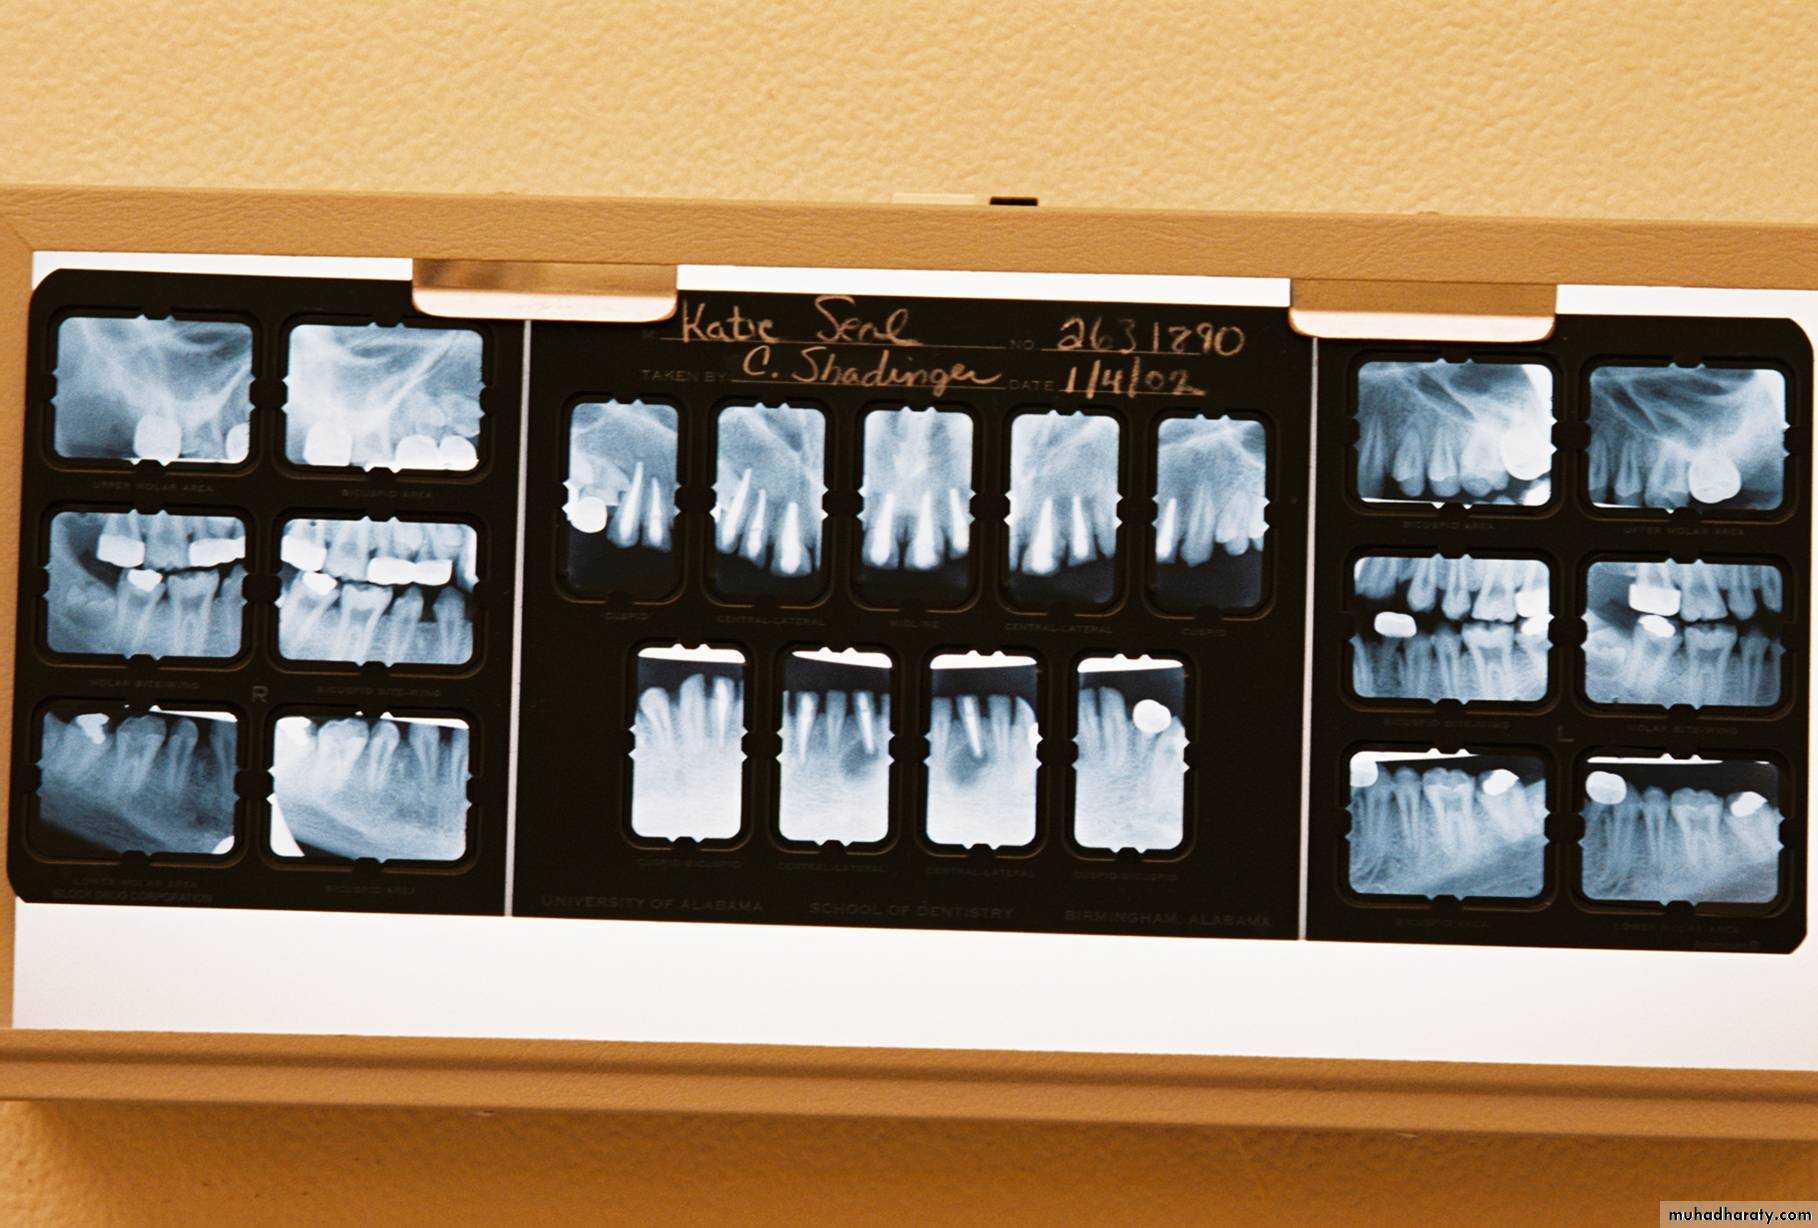

Evaluation of radiographic survey

All prospective abutment teeth must be critically evaluated4/2/2018

Root size, length and form

Teeth with large or long roots - Greater periodontal supportTapered or conical roots- un favorable

Multi rooted teeth with divergent roots are stronger abutment teeth than single rooted, multi rooted teeth with fused roots.4/2/2018

Signs of positive bone factor

A supportive trabecular patternHeavy cortical layer

Dense lamina dura

Normal bone height

Normal periodontal ligament space.

If retrograde bone changes occur, the patient has a negative bone factor ; prognosis is poor.